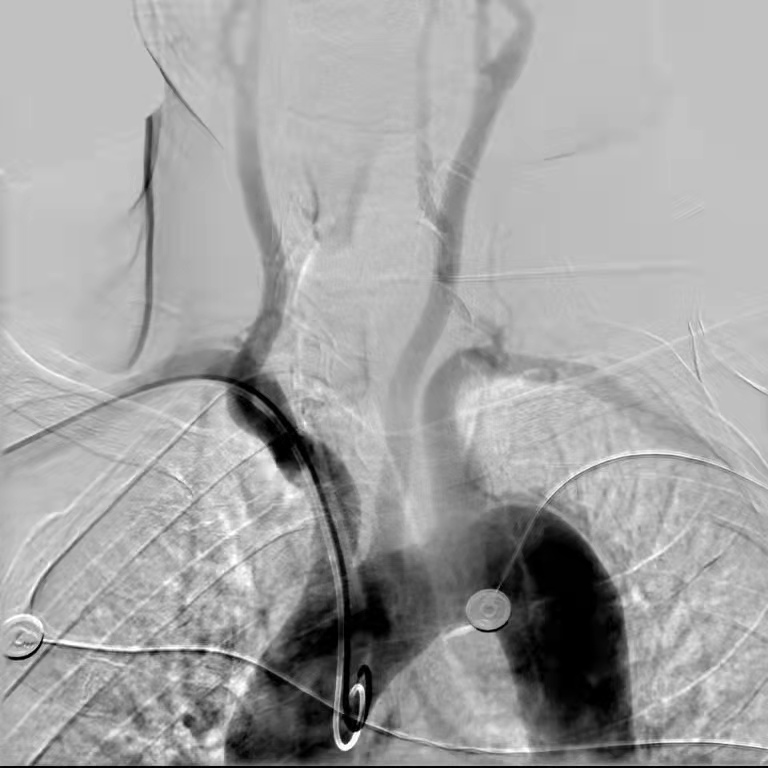

近日,在我院神经内科介入团队及导管室团队通力合作,顺利开展了医院首例经远端桡动脉穿刺脑血管造影术,为神经介入诊疗技术的开展提供了新的选择方式。

为更好地服务患者,神经内科介入团队不断追求技术创新。近日,科室黄骏主治医师成功为患者实施了新途径——远端桡动脉穿刺术完成脑血管造影,穿刺点选择在第一与第二掌骨之间的鼻烟壶区,对准桡动脉远端的分支血管进行穿刺插入导丝导管,穿刺过程顺利,患者没有明显疼痛感。该患者术后2小时即拆除了止血带,手部活动自如。

科室主任刘波表示,近年来我国脑血管疾病发病率居高不下,远端桡动脉穿刺具有动脉波动点易触及、穿刺简单、不损伤桡动脉、易压迫、术者易操作、患者舒适等优点,可以减少大出血、前臂附近桡动脉闭塞等风险,术后恢复更快,除穿刺侧腕关节外,其余肢体关节在术后活动不受限制。这对于不能坚持卧床的老年患者来说,优势更为明显,而术后卧床制动时间减少对于降低下肢深静脉血栓形成的发生具有积极意义,为病人提供了更舒适就医体验。

桡动脉远端穿刺作为神经介入新的途径,填补了院内技术空白,是省内先进技术。开展经远端桡动脉穿刺行全脑血管造影术,为后期复杂血管内治疗奠定技术基础,也为医院高级卒中中心建设丰富技术手段。